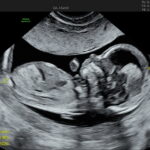

When Can You Get It Done?

You can take the test as early as 10 weeks of pregnancy, giving you a head start in understanding your baby’s well-being.